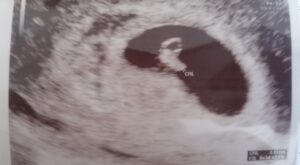

Sera positiva ayudaaa

Non classé

hay 9 años